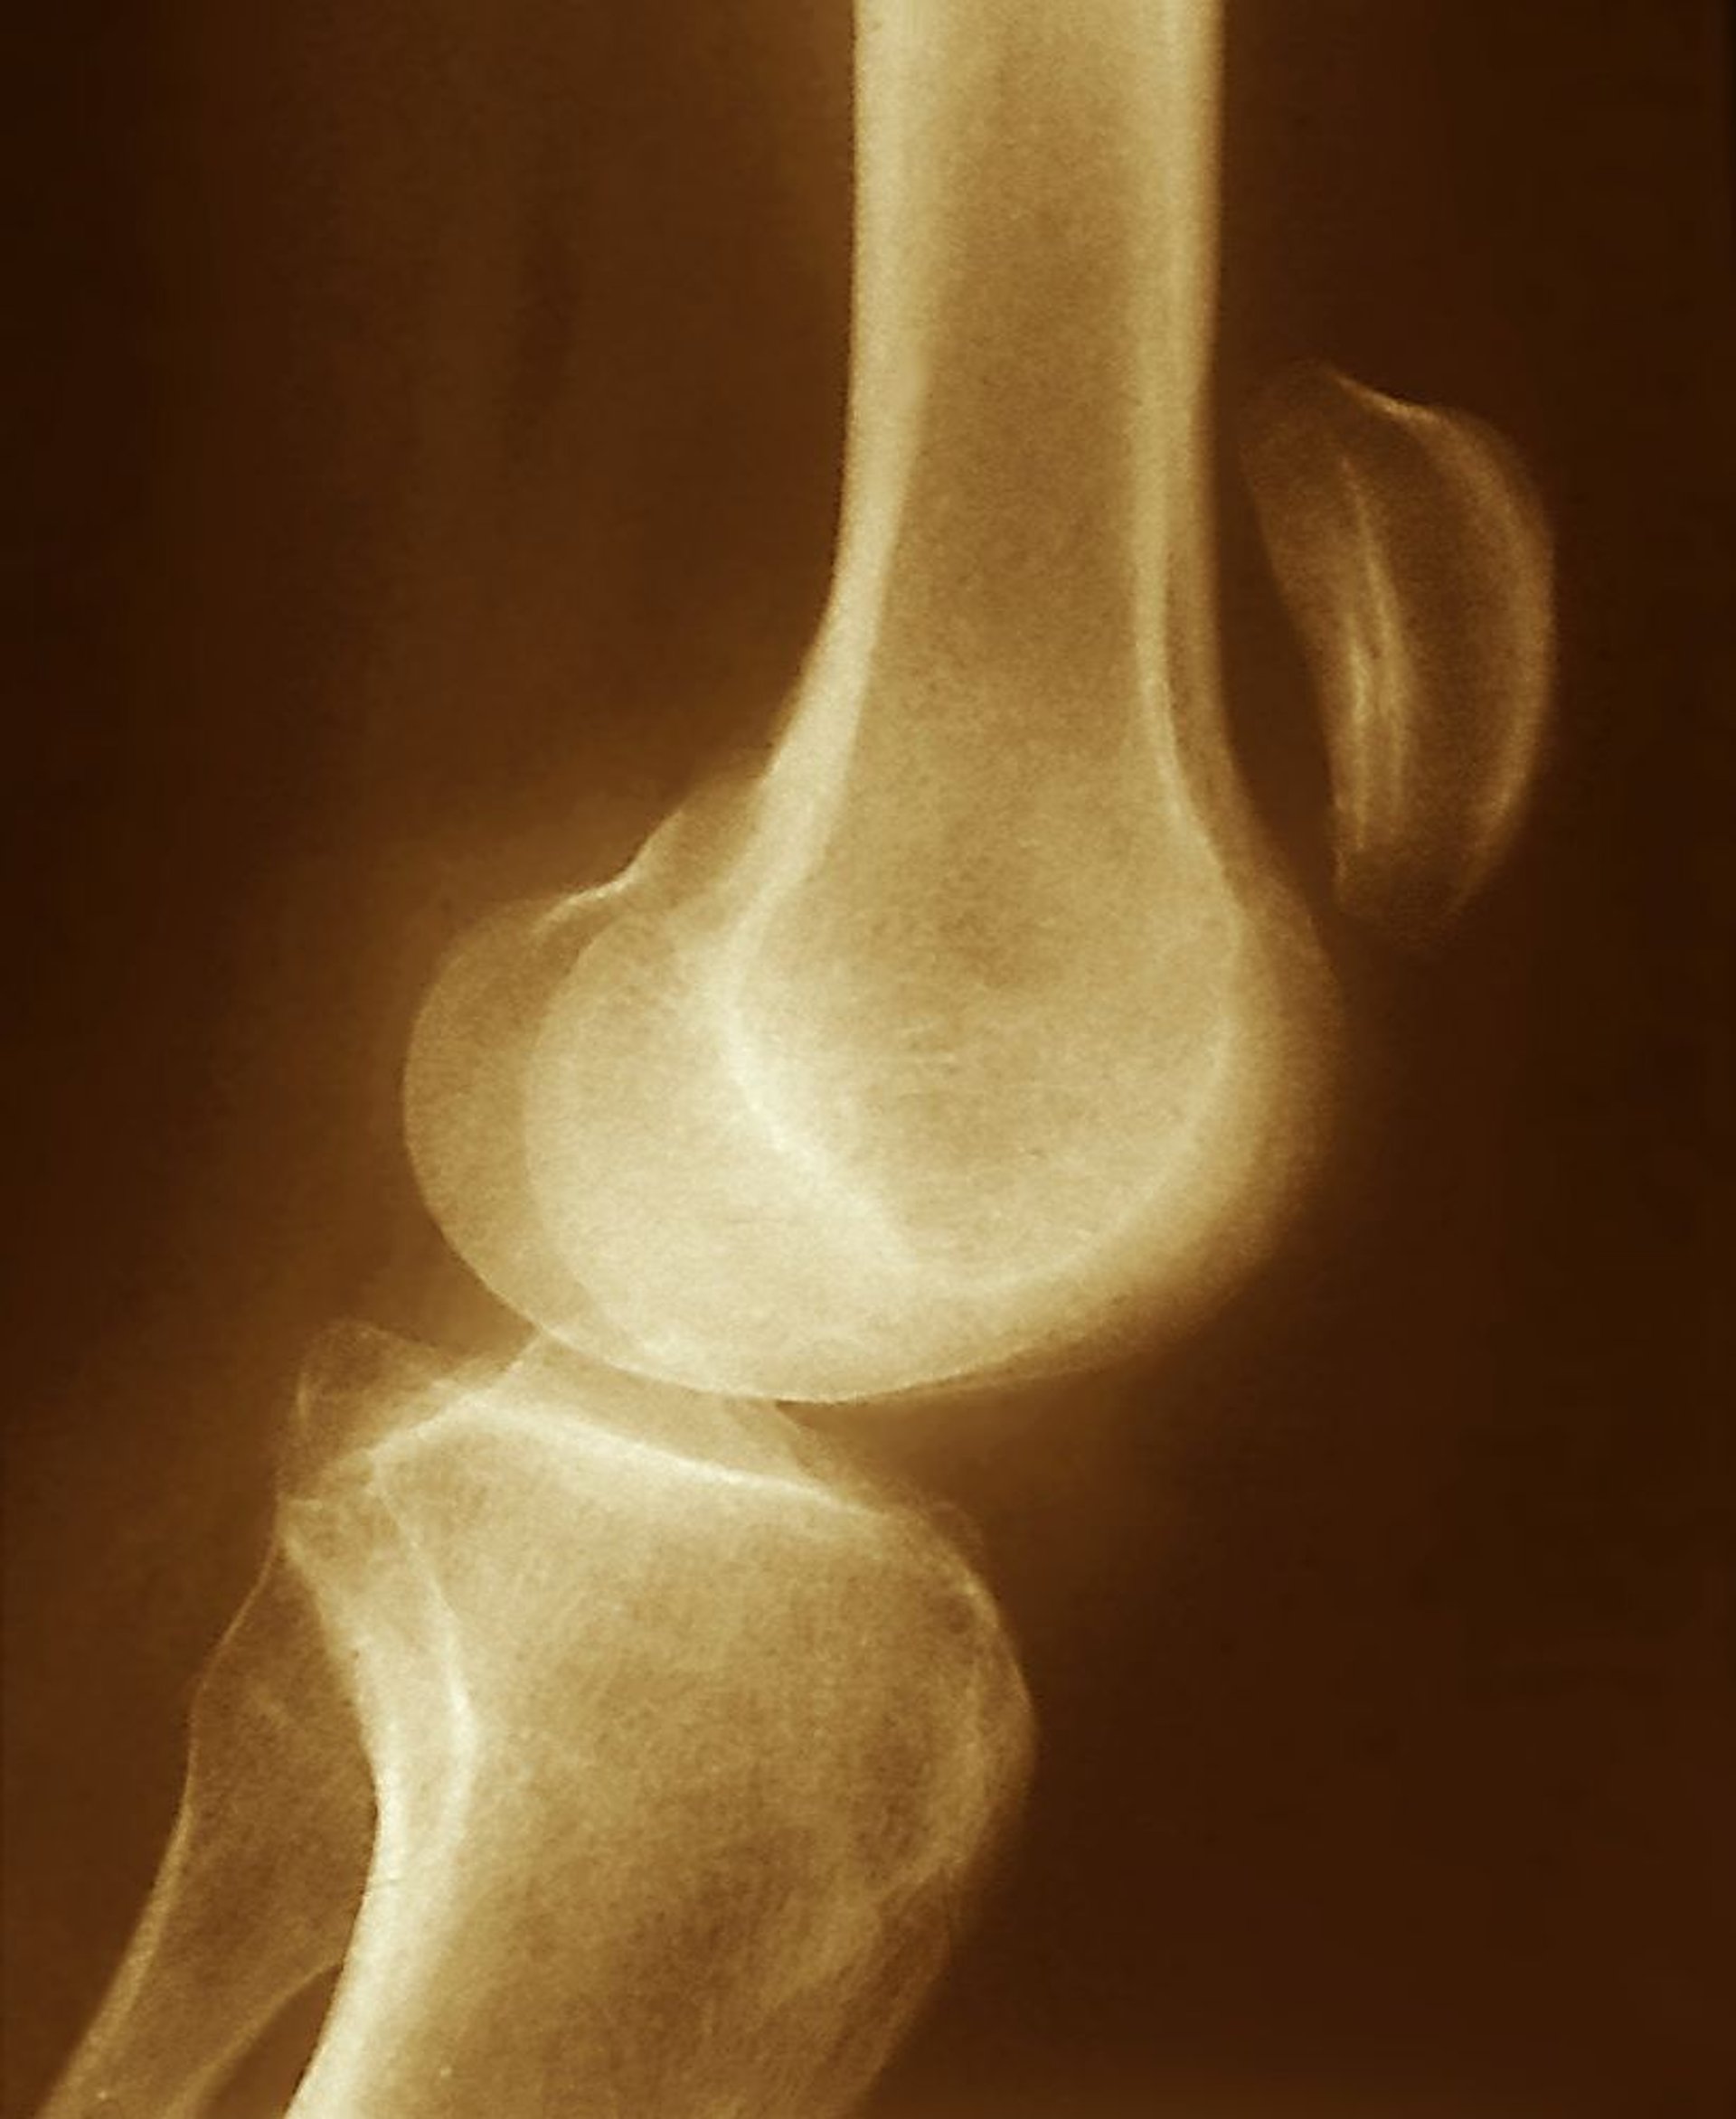

Patellar Tendon Tear

The superior displacement of the patella seen on this radiograph (well above the knee joint) suggests a tear of the patellar tendon, with unopposed contraction of the quadriceps muscle.